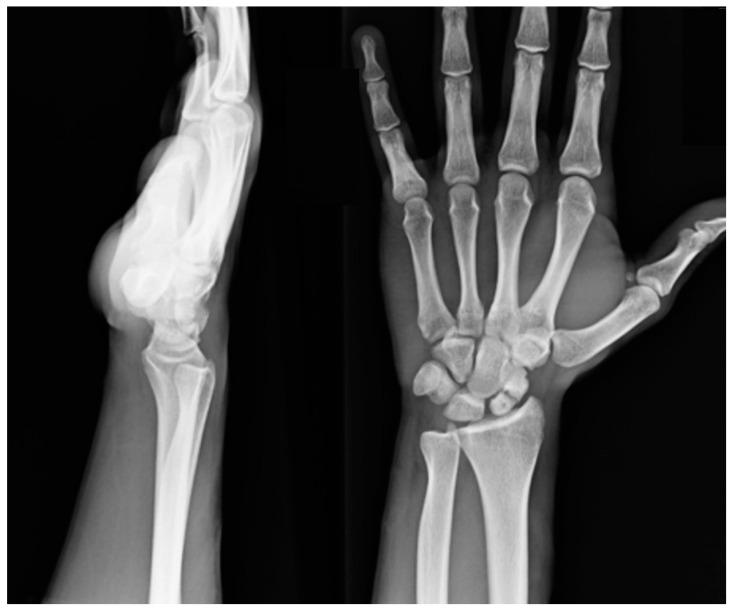

Treatment of scaphoid fracture sequelae is still an unsolved problem in hand surgery. Custom-made 3D-printed titanium partial and total scaphoid prosthesis and scaphoid interosseous ligament reconstruction (SLIL) are performed in cases of non-union and isolated aseptic necrosis of the proximal scaphoid pole and when it is impossible to save the scaphoid bone, respectively. This study aims to evaluate the clinical, functional and radiographic results after these two prosthesis implantations.

Between January 2019 and July 2020, nine partial and ten total scaphoid prostheses were implanted using custom-made 3D-printed titanium implants. Evaluation criteria included carpal height ratio (CHR), radioscaphoid angle, wrist extension and flexion, radial deviation and ulnar deviation of the wrist, grip strength and pinch strength, Visual Analogue Scale (VAS), the Disabilities of Arm, Shoulder, and Hand (DASH) score, and the Patient-Rated Wrist Evaluation (PRWE).

舟骨骨折后遗症的治疗仍是手外科尚未解决的问题。对于舟骨不愈合和舟骨近端孤立性无菌性坏死,以及无法保留舟骨的情况,分别采用定制的3D打印钛质舟骨部分和全舟骨假体以及舟骨骨间韧带重建术(SLIL)。本研究旨在评估这两种假体植入后的临床、功能和影像学结果。

2019年1月至2020年7月期间,使用定制的3D打印钛植入物植入了9个舟骨部分假体和10个全舟骨假体。评估标准包括腕骨高度比(CHR)、桡舟角、腕关节伸展和屈曲、腕关节桡偏和尺偏、握力和捏力、视觉模拟量表(VAS)、上肢、肩部和手部功能障碍(DASH)评分以及患者自评腕关节评估(PRWE)。